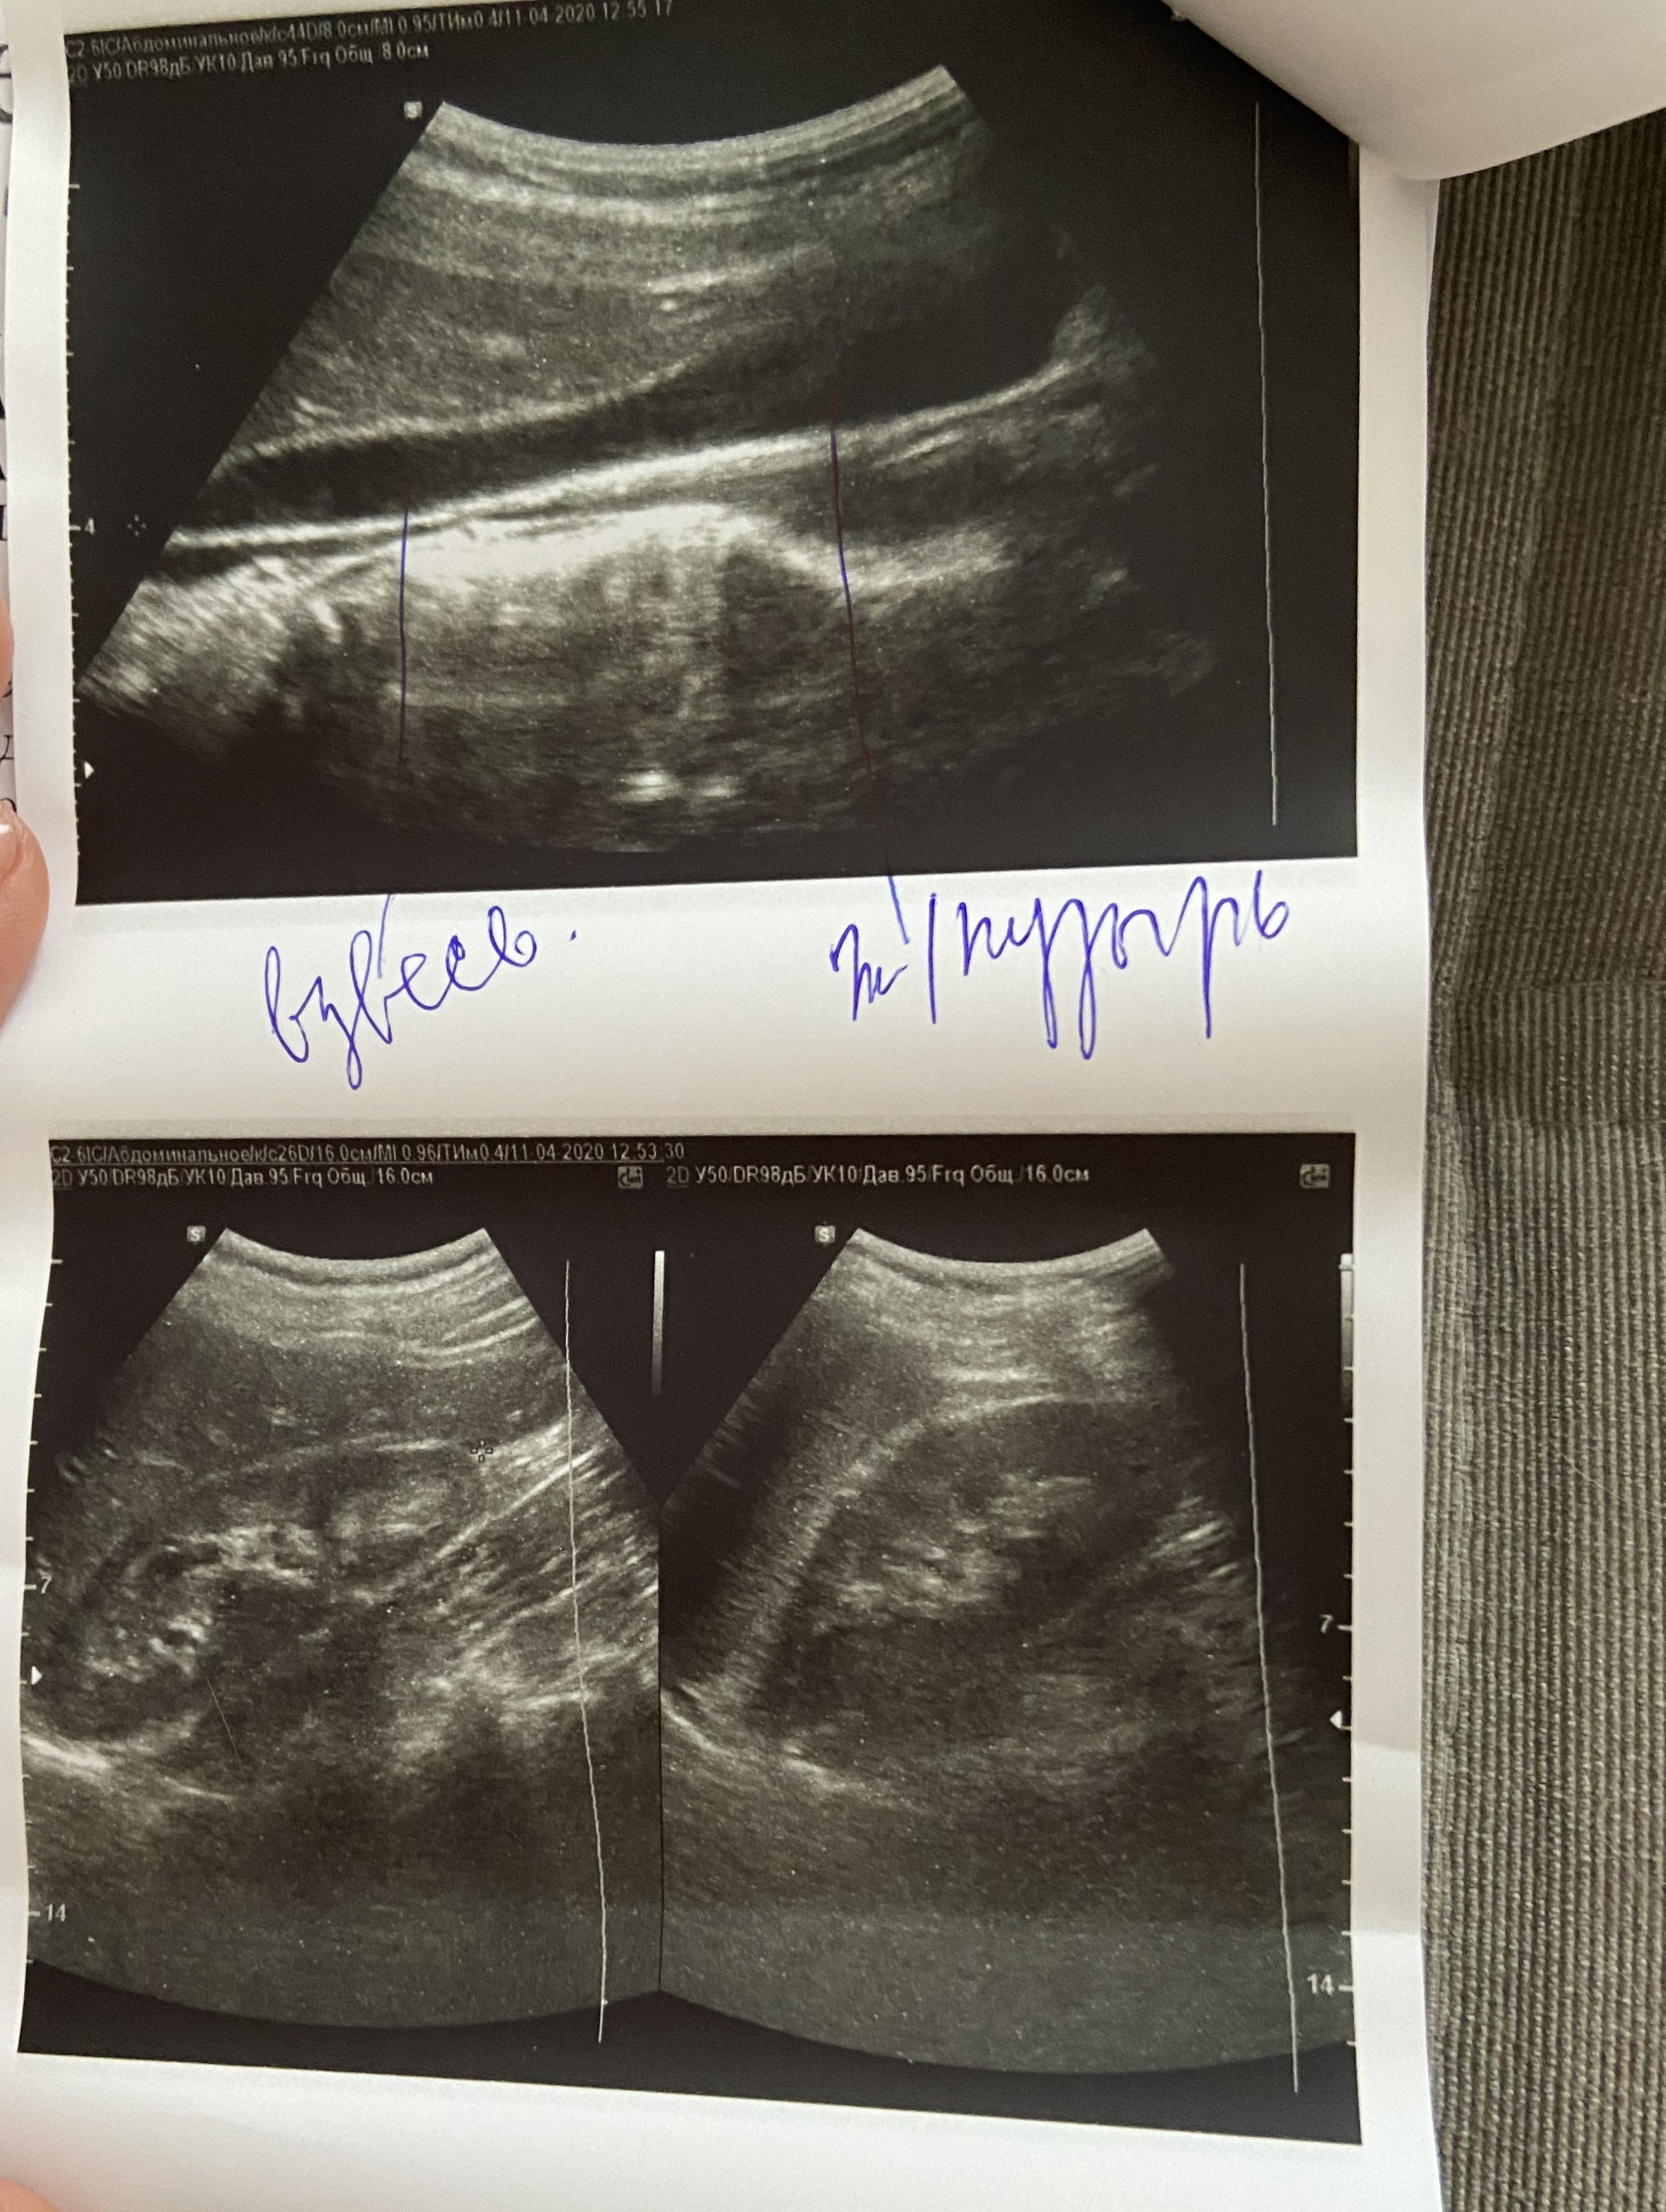

Завтра прикреплю узи.Нашла у себя сосудистые звездочки и мне очень страшно

Спасибо Всем большое,так приятна эта поддержка)))Не смогла ещё разобраться,как отвечать на личные сообщения,сейчас буду смотреть и выкладывать узи...Посмотрите ,пожалуйста

Хочу поскорее начать лечение и заказать препараты))Как считаете по результатам узи ,можно заказывать соф+вел,без рибавирина или дождаться анализов крови?

По результатам УЗИ нет ничего критичного. Диффузные изменения поджелудочной и хронический холецистит частые спутники гепатитчиков. Хорошо, что камней в желчном нет. Для улучшения самочувствия можно обойтись регулировкой режима питания, исключением продуктов, вредных для желчного, приёмом желчегонных препаратов.